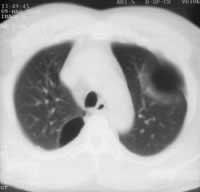

Чаще буллы выглядят как одиночные и множественные округлые полости, но встречаются и многокамерные буллы. Так же высока информативность метода РКТ при парамедиастинальных буллах (Рис. 2), которые практически не выявляются другими методами. Только с помощью компьютерной томографии можно идентифицировать каждую буллу, установить их количество, размеры и локализацию (Рис. 3).

Рис. 3. Множественные буллы в левом реберно-диафрагмальном синусе.